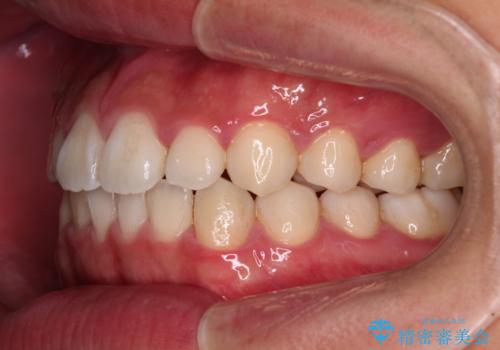

- 20代男性

- インビザライン・ライト

- 上下前歯の叢生を気にして来院された患者様です。

費用を抑え、期間もあまりかけずに治療をしたいとのことで、インビザライン・ライトを用いて矯正治療を行うこととしました。